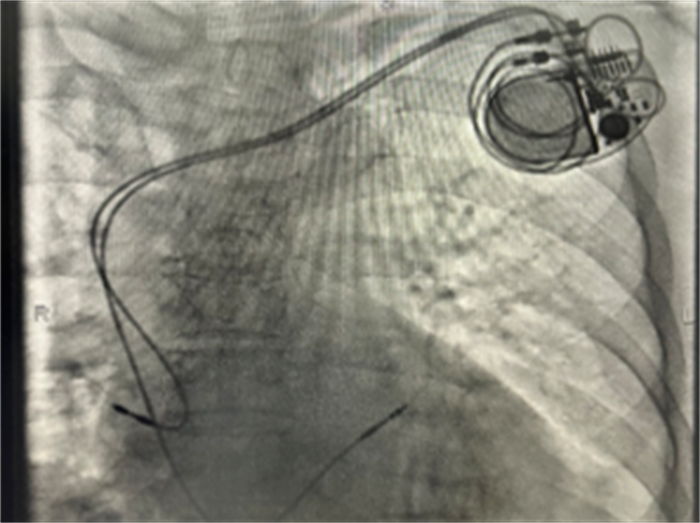

在上级医院专家的指导下,该院心内科团队默契配合、细致操作,历时75分钟,顺利完成首例永久性双腔心脏起搏器植入术。术后,起搏器工作正常,患者感觉良好,安返病房。

| 77岁高龄患者已成功植入双腔起搏器 |